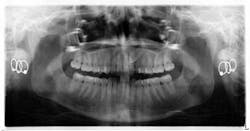

When a full permanent dentition is present (with the exception of impacted canines), the labial/palatal position of the canine will have an influence on what the provider can do. (1) Arguably, obtaining a CBCT is considered mandatory and will allow for a more inclusive treatment plan creation. If angulation is favorable, then consideration to remove the primary canine and wait six months to see if there is movement of the permanent canine is an option. If extraction of the canine(s) is needed, then a premolar substitution, which is dependent on occlusion, can be used in the space. An implant can also be an appropriate alternative. When pulling a canine into the occlusal arch, there is risk involved. Trauma to adjacent teeth (root resorption) and ankylosis are some of the most common complications.The patient was put in full orthodontics and referred to a surgeon for extraction of the primary canines, exposure, and placement of retention on the impacted canines to pull them directly down from their current position.

A ballista appliance was used to prevent a facial pull of the canines in order to avoid and prevent resorption of the roots of the lateral incisors. As movement progressed over the course of the next year, eruption of the canines was considered a success. Once in position, they will be pulled facially into occlusion.